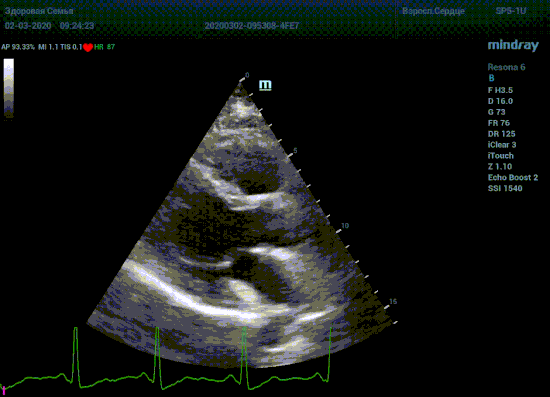

Специалисты в области эхокардиографии прекрасно знают о важности точного и скрупулёзного измерения. Рекомендации зарубежных кардиологических и эхо кардиографических обществ описывают эхокардиографию только под контролем ЭКГ. Многие клиники в России до сих работают без ЭКГ канала, выбирая кадры для измерения «на глазок». Результаты таких исследований менее точны и воспроизводимы, однако роль их очень и очень велика. Часть клиник используют ЭКГ отдельно от прибора, на бумаге. В таком виде для эхокардиографии она бесполезна, по сколку не создает временной карты для измерений.

Подбор подобающей терапии и оценка её динамики на базе расчета массы миокарды рутинная задача эхокардиографии. Для измерения массы нужен кадр конца диастолы. На глазок или точно, по ЭКГ каналу, выбрать диастолу? Гипертрофия миокарда или его ремоделирование? Ремоделирование или норма? Решает каждый измеренный миллиметр, даже каждая его десятая. Лишние доли секунды приведут к началу сокращения миокарда и его утолщению, в результате -гипердиагностика.